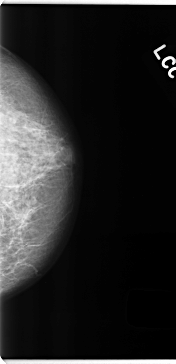

C_0193_1.LEFT_CC

LEFT_CC LINES 4720 PIXELS_PER_LINE 2280 BITS_PER_PIXEL 12 RESOLUTION 50 NON_OVERLAY